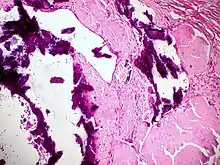

Amyloidosis, dystrophic calcification

Amyloidosis, blood vessels, H&E